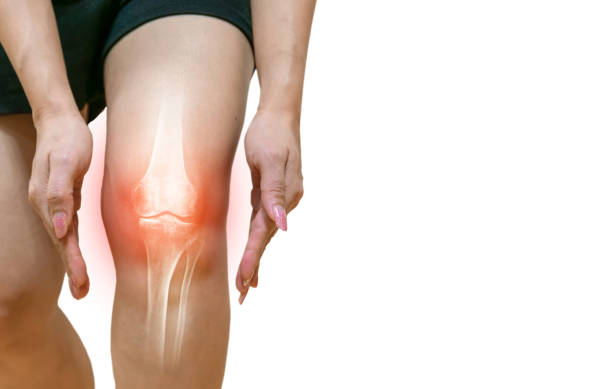

무릎 통증 원인 초기 치료 자세히 알아보기

무릎 통증이 초기에 발견되고 적절한 치료를 받으면, 심각한 상태로 악화되는 것을 예방할 수 있습니다. 무릎 관절은 몸의 중심부에 위치하고 있어, 무게 중심의 일부를 지지하며, 매우 복잡한 기구로 구성되어 있습니다. 따라서 무릎 관절의 이상은 다양한 원인과 증상을 보일 수 있습니다. 초기에 발견하여 조치를 취하지 않으면, 무릎 관절은 더 큰 문제로 발전할 수 있어 이번 시간에는 무릎 통증 원인과 초기 치료에 대해 알아보겠습니다.